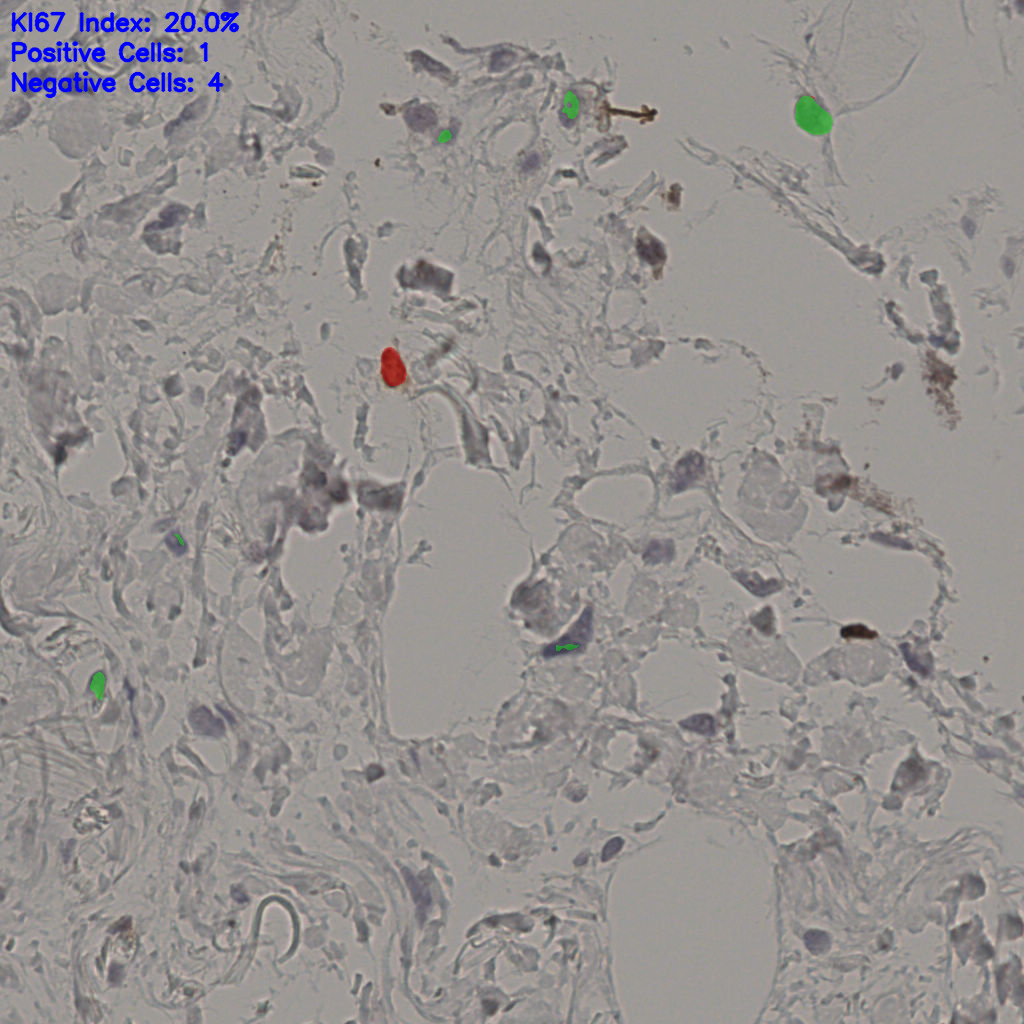

17.75%

Ki67 指数

阴 7986 阳 1723

总切片 2640

有效 412

已标记 412

有效率 16%